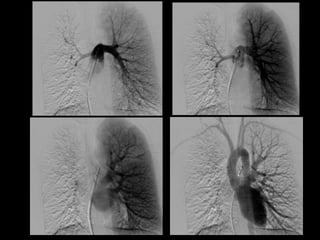

Resangrado tras embolización

• Oclusión incompleta de los vasos implicados.

• Recanalización de los vasos implicados.

• Desarrollo de nuevas colaterales.

• Tratamiento inadecuado de patología

subyacente.